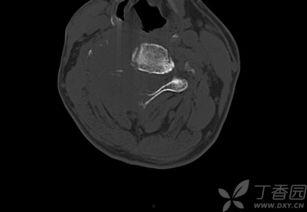

放疗的成功案例数不胜数。以下是一张放疗成功案例的图片,展示了患者在接受放疗后肿瘤明显缩小的效果。